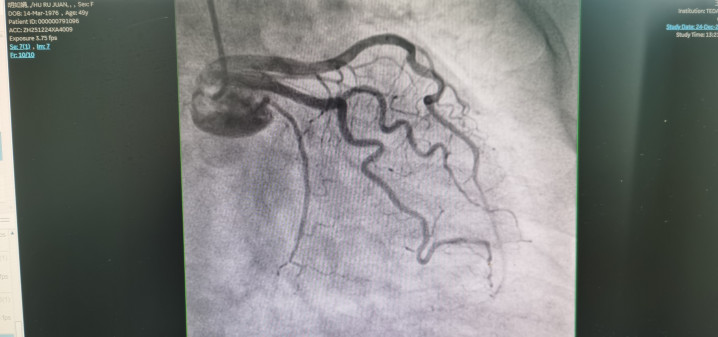

冠状动脉造影